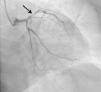

Foi ativada a equipa de hemodinâmica e iniciou medicação com dose de carga de ácido acetilsalicílico (AAS) (300mg) e ticagrelor (180mg) e heparina não fracionada (5000 unidades). Realizou cateterismo emergente (menos de uma hora após o início da dor torácica), que mostrou uma lesão proximal suboclusiva na artéria descendente anterior (DA), marcadamente calcificada e com imagem de trombo (Figura 3). Visualizou‐se também um ramo intermédio com lesão ostial de cerca de 50%, coronária direita com lesão inferior a 50% no segmento médio e circunflexa sem lesões significativas. Realizou angioplastia primária da DA proximal, com trombectomia e remoção de material trombótico, pré‐dilatação com balão e colocação de stent impregnado com fármaco (SIF) na DA proximal, cobrindo a origem da primeira diagonal.

Neste caso, assumiu‐se o diagnóstico de SK tipo II dada a presença de uma reação alérgica (sendo confirmada posteriormente a alergia a veneno de himenóptero), concomitantemente a uma SCA, com documentação de DAC (trombo suboclusivo na DA proximal). Não foram determinados os valores de triptase, histamina, IgE total e complemento, mas estes não excluem nem confirmam o diagnóstico, que é essencialmente clínico.